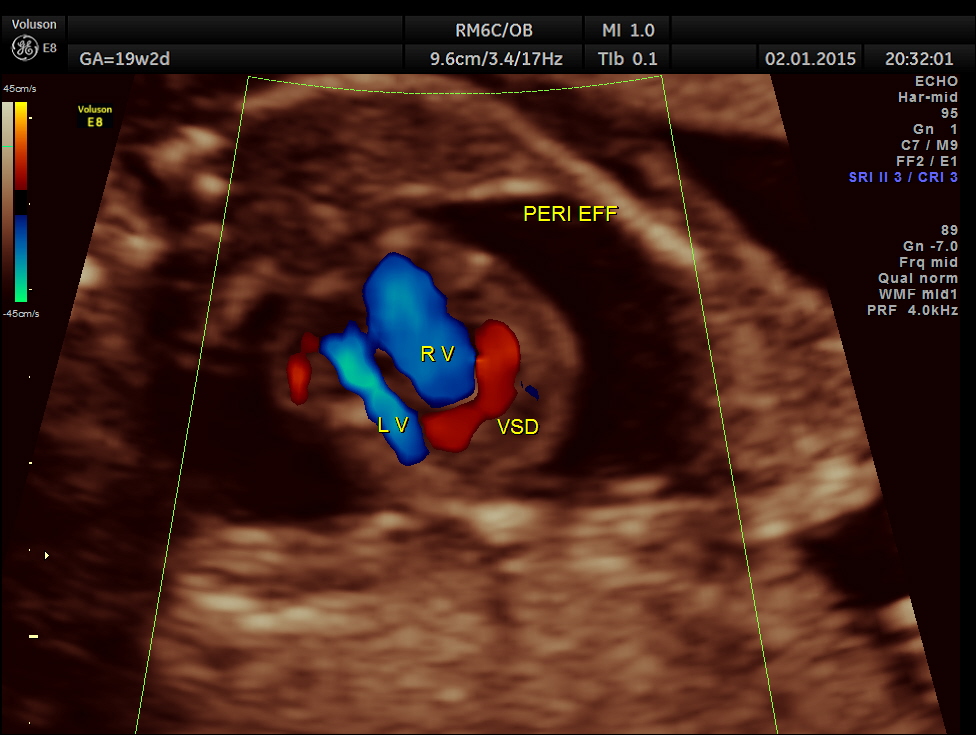

A large pericardial effusion is seen.

A prominent muscular ventricular septal defect is seen.

Apart from the VSD , left heart appears disproportionately smaller.

Great vessel crossing is seen.

This fetus had a large pericardial effusion with structural defect of the heart – VSD and disproportionately smaller left heart – possibly co-arctation of aorta . The patient was advised chromosomal studies and was lost for follow up.